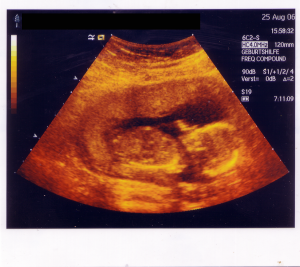

The Nebraska legislature passed a law, LB599, that restored funding for prenatal care for the unborn children of undocumented immigrants. That didn’t sit well with Nebraska’s Governor, Republican Dave Heineman, who took out his veto pen and nullified the law, saying that spending public funds on the undocumented was money ill spent. And although the law had to do with health care and prenatal attention, there were obvious underlying issues at hand – immigration being the most obvious, abortion being more inferred. The link to abortion has to do with two things: a recourse or option for women who lack support for the care of their unborn child; and the debate about the beginning of life – does life begin at the moment of conception?

The drawn-out drama over the issue came as a consequence of Nebraska’s rule where three votes were needed to pass the law. When the three hurdles were cleared, the law made it’s way to the Governor’s desk where it hit the veto wall. As it stood, the unborn children of undocumented mothers were denied prenatal care because the Governor of Nebraska didn’t consider them citizens, yet – and that was a large enough loophole for him to slip through and pitch a tent.

The ideological problem for Heineman, which he chose to ignore, was that his anti-abortionist stance infers a belief that life begins at the moment of conception, so that the unborn are already persons, and if they’re persons they must have citizenship, presumably U.S. citizenship, regardless of the citizenship of the mother. So under that logic there’s no reason to deny them care.

[Photo by Achim Raschka]